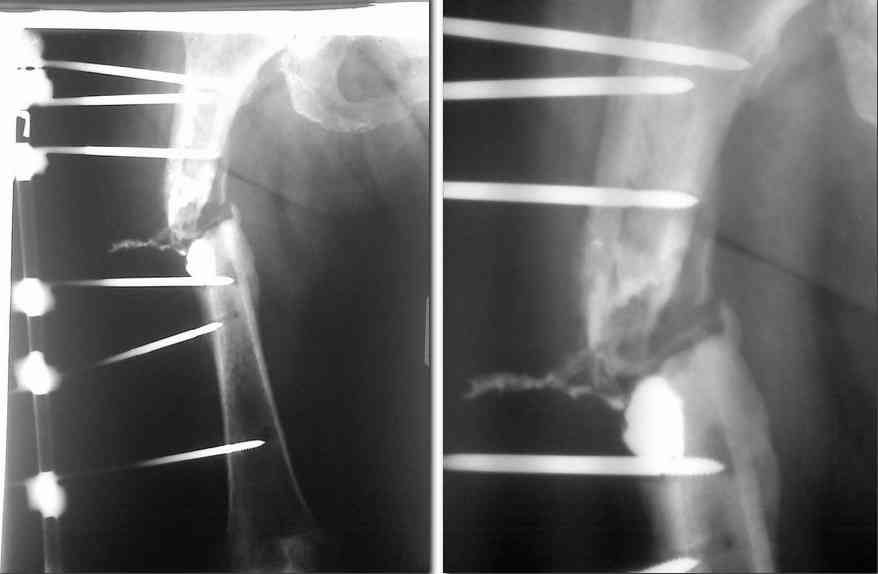

Здравствуйте, уважаемые коллеги. Обратилась женщина 63 года с неконсолидированным

переломом правого бедра, остеомиелитом бедра, фистульная форма.

Анамнез со слов больной: травма около 2 лет назад, синтез пластиной,

консолидация не наступила, ресинтез интрамедулярным стержнем, через

3-4 месяца после операции в области рубца образовался свищ. В феврале

2010 года выполнена фистулонекректомия с удалением стержня, фиксация

одноплоскостным аппаратом внешней фиксации, рана зажила, ходила на костылях. 3 месяца

назад отметила воспаление вокруг стержней, боль, образовались свищи, бедро

деформировалось, 2 месяца назад перестала ходить в связи с усилением боли.

В момент поступления: укорочение бедра 4-5 см, в области

послеоперационного рубца 2 свищевых отверстия 1-1.5 см в диаметре, по

передней поверхности бедра свищ 1.5см в диаметре, выделяется густой

гнойный ексудат. Вокруг стержней воспалительная реакция,

серозно-гнойная ексудация. Патологическая подвижность. Посев-роста

нет. Фистулограма в приложении.

Аппарат демонтирован, скелетное вытяжение. Раны в местах стержней зажили.

Вчера прооперирована: фистулонекректомия, экономная резекция концов фрагментов,

фиксация с укорочением и компрессией в спице-стержневом АВН (5 стержней в проксимальном

фрагменет по передней и внешней поверхности и 2 кольца на 4 спицах в дистальном фрагменте)